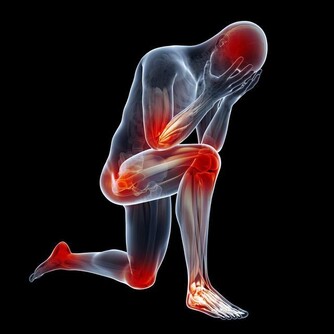

在日常生活和工作中,人們經常會被各種原因導致的“膝蓋”疼所困擾,並逐漸朝著年輕化發展,很多時候,往往因為疼痛程度小,時間段而被人們所忽視,並因此落下“病根”,為以後的生活帶來困擾,今天和大家一起掰扯掰扯那些被你忽略的膝蓋疼到底都是怎麼回事。

哪些常見的損傷會引起“膝蓋”疼?

1.軟組織損傷

軟組織損傷通常指皮膚、皮下、肌肉或是韌帶的損傷,主要原因是由於暴力引起的纖維結締組織撕裂所造成的,這種暴力主要是由於外界暴力或本身運動過度以及熱身不足產生,一旦出現損傷,會伴隨著皮膚、肌肉疼痛,乃至腫脹發生。

2.半月板損傷

半月板是一種彈性軟骨,位於股骨遠端與脛骨平台之間起緩衝作用,防止關節面軟骨受衝擊造成的損傷。半月板損傷主要由於外界暴力引起,也可以由自身退變引起。主要表現為屈伸活動時發生在關節內的彈響或突然“卡住”,多是因為破裂的半月板與脛骨、股骨發生異常的摩擦或嵌頓而產生。

3.膝關節滑膜炎

膝關節是全身關節中滑膜最多的關節,故滑膜炎以膝關節較為多見。膝關節滑膜炎通常指膝部的滑膜受到刺激而引發炎症,進而分泌液失調在關節腔內形成積液的一種病變,包括非特異性滑膜炎和特異性滑膜炎。當關節受外在性和內在性因素影響時,滑膜發生反應,引起充血或水腫,並且滲出液體,表現為關節腫脹、疼痛、關節腔積液、活動受限等。如不及時治療,會影響關節正常活動,並造成關節的破壞甚至病廢。

4.膝關節炎

膝關節炎是一種由膝關節軟骨退行性改變引起的疾病,引起疾病的原因包括年齡、性別、遺傳因素、重複性關節應激和代謝紊亂,病變影響軟骨、軟骨下骨和關節組織,主要特徵為關節軟骨的漸進性破壞與軟骨下骨的硬化,骨贅形成,與滑膜炎有關,臨床症狀表現為劇烈疼痛、關節僵硬、關節活動度顯著降低,有甚者可能進一步導致殘疾發生,嚴重影響患者的生活質量。

除此之外,常見的還有痛風、肥胖、風濕性關節炎以及類風濕性關節炎等都會引起“膝蓋”疼,由此可見,我們需要對此引起高度的重視,做到“早發現,早治療”,防止由於個人忽視導致疾病逐漸加重、惡化,進而對家庭和日常生活產生不良影響。